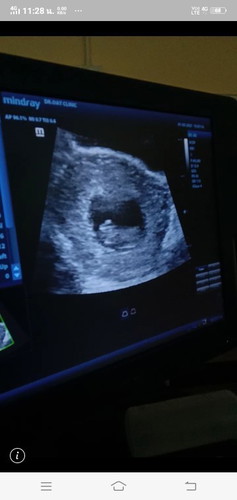

เจอน้องแล้วค่ะ หัวใจเต้นปกติจ้า

กำลังตั้งครรภ์

8สัปดาห์ค่ะ